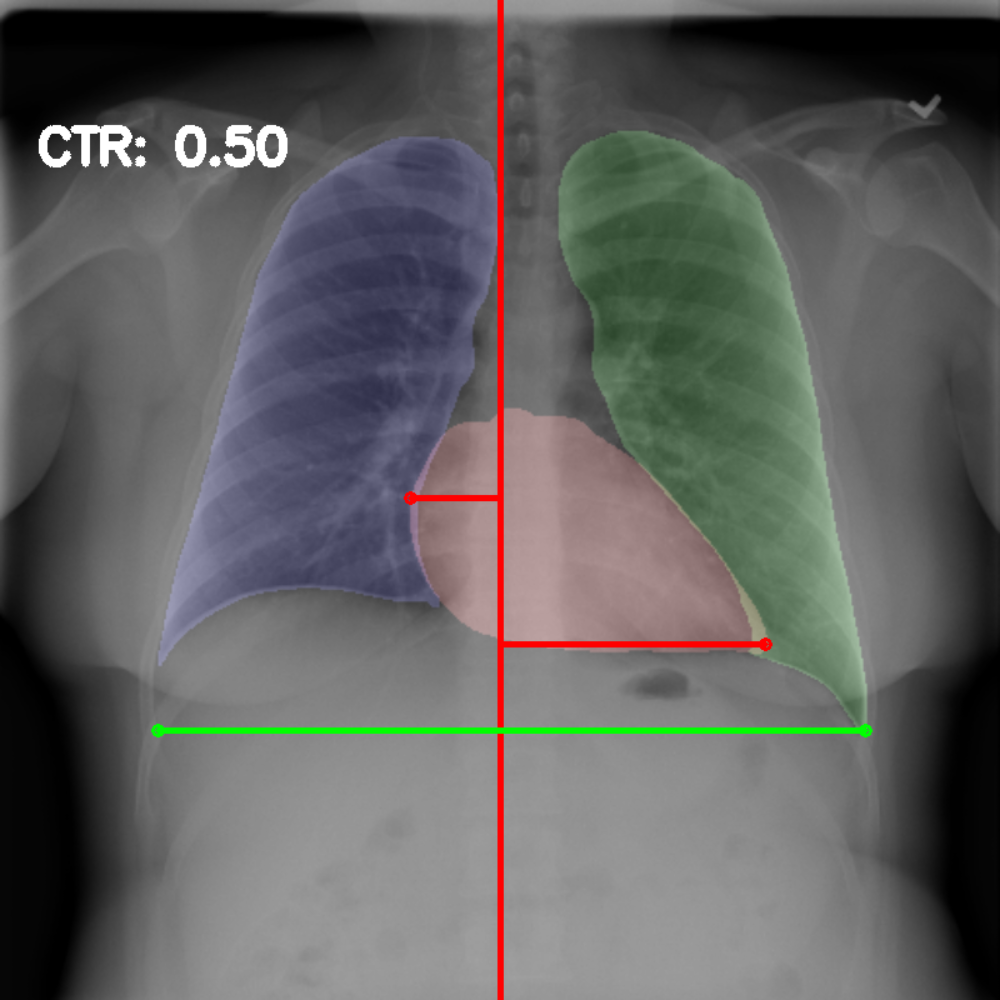

Chest radiography is the most common tool for detecting cardiomegaly due to the low cost and high availability of devices to obtain chest X-ray images. From chest X-ray images, radiologists employ CTR as one of the most important indicators of cardiomegaly due to the simplicity of the calculation. CTR of a chest X-ray image is calculated as cardiac diameter (the diameter of the heart) divided by the thoracic diameter (the diameter of the chest). Specifically, CTR can be calculated from three measurements, , the midline-to-right heart diameter, , the midline-to-left heart diameter, and , the internal diameter of chest [2, 3], as

| (1) |

where and is measured from the greatest perpendicular diameter from midline to right and left heart border, respectively. Figure 1 visualizes the details of CTR calculation. A CTR value of is generally considered to indicate the upper limit of normal.

3.5 Cardiothoracic Ratio Calculation

After obtaining the masks, we calculate CTR with equation 1. We calculate cardiac diameter, , by finding the extreme points on the x-axis of the heart mask and calculate their x-axis distance. Thoracic diameter, , is calculated from extreme points from the lung mask. Figure 4 demonstrates the calculation of each component.

After obtaining heart and lung segments, we calculated , , and and marked them on the image along with CTR value calculated from Equation 1.

Figure 6 shows examples of our CTR calculation, where CTR values along with their , and measurement points are correctly identified. In this image, cardiomegaly is correctly detected by CTR value of .